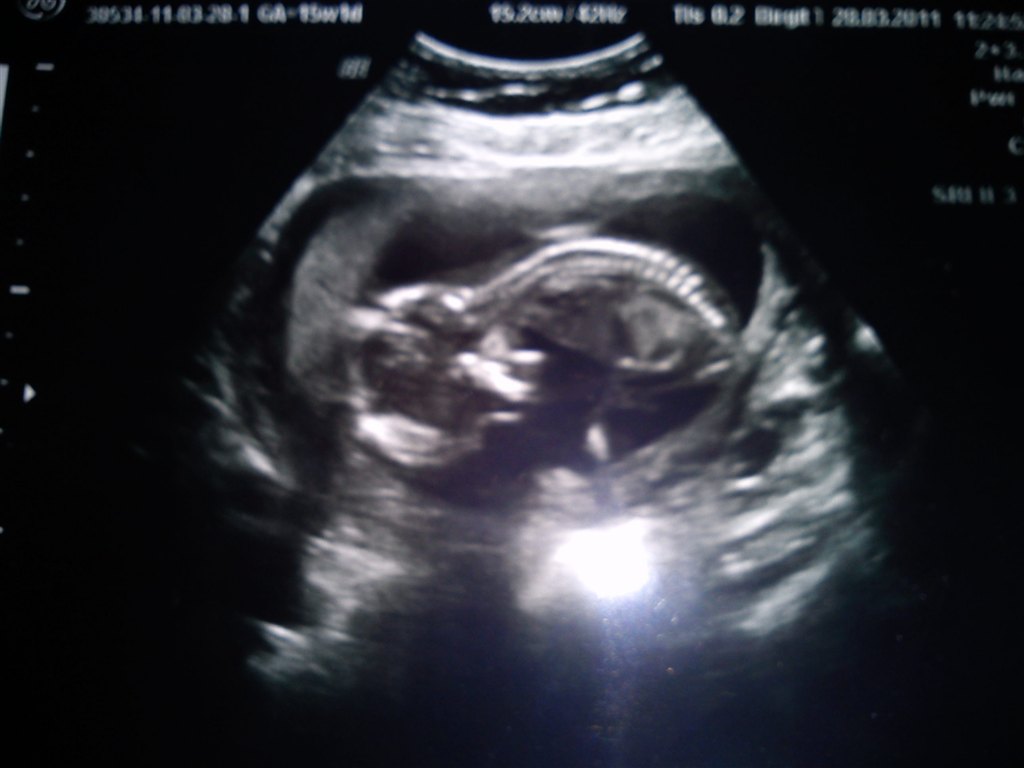

15+1 a